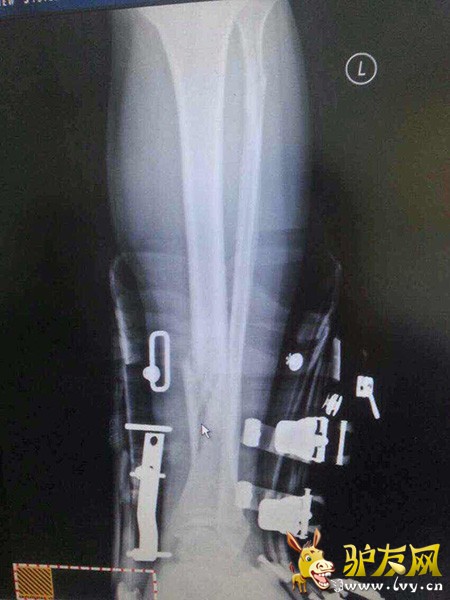

北京时间12月18日消息,据微博认证用户微博上爆料,央视体育频道著名主持人韩乔生今早滑雪意外受伤,小腿两处骨折,伤势严重。

微博认证信息为“国家一级裁判”的黄川-77今日下午在微博上称,“央视名嘴韩乔生今天上午在崇礼云顶滑雪场玩雪地自行车撞上一位正在滑雪的美女,因为美女全身护甲装备齐全,并无大碍,韩老师则小腿两处骨折,伤势较严重。骨折处在雪鞋内部,现在如何脱掉硬雪鞋成为难题。”